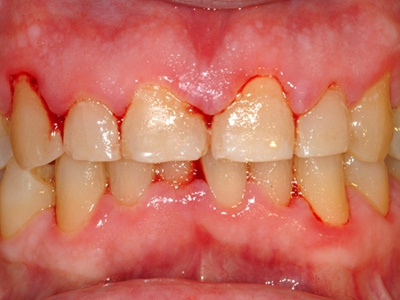

牙龈炎是发生于牙龈组织的炎症,患者可出现牙龈出血伴肿胀、发红、正常形态改变和偶尔不适等症状。本病主要由口腔卫生状况差导致,包括口腔不洁、牙菌斑等,诊断依据临床检查,治疗包括专业牙齿清洁和加强家庭口腔卫生。

牙龈炎可先引起牙齿与牙龈之间的沟(龈沟)加深,然后牙龈充血,炎症围绕一个或多个牙齿,伴牙龈乳头肿胀和易出血。一般无痛,可自行消退,也可维持轻度炎症数年。